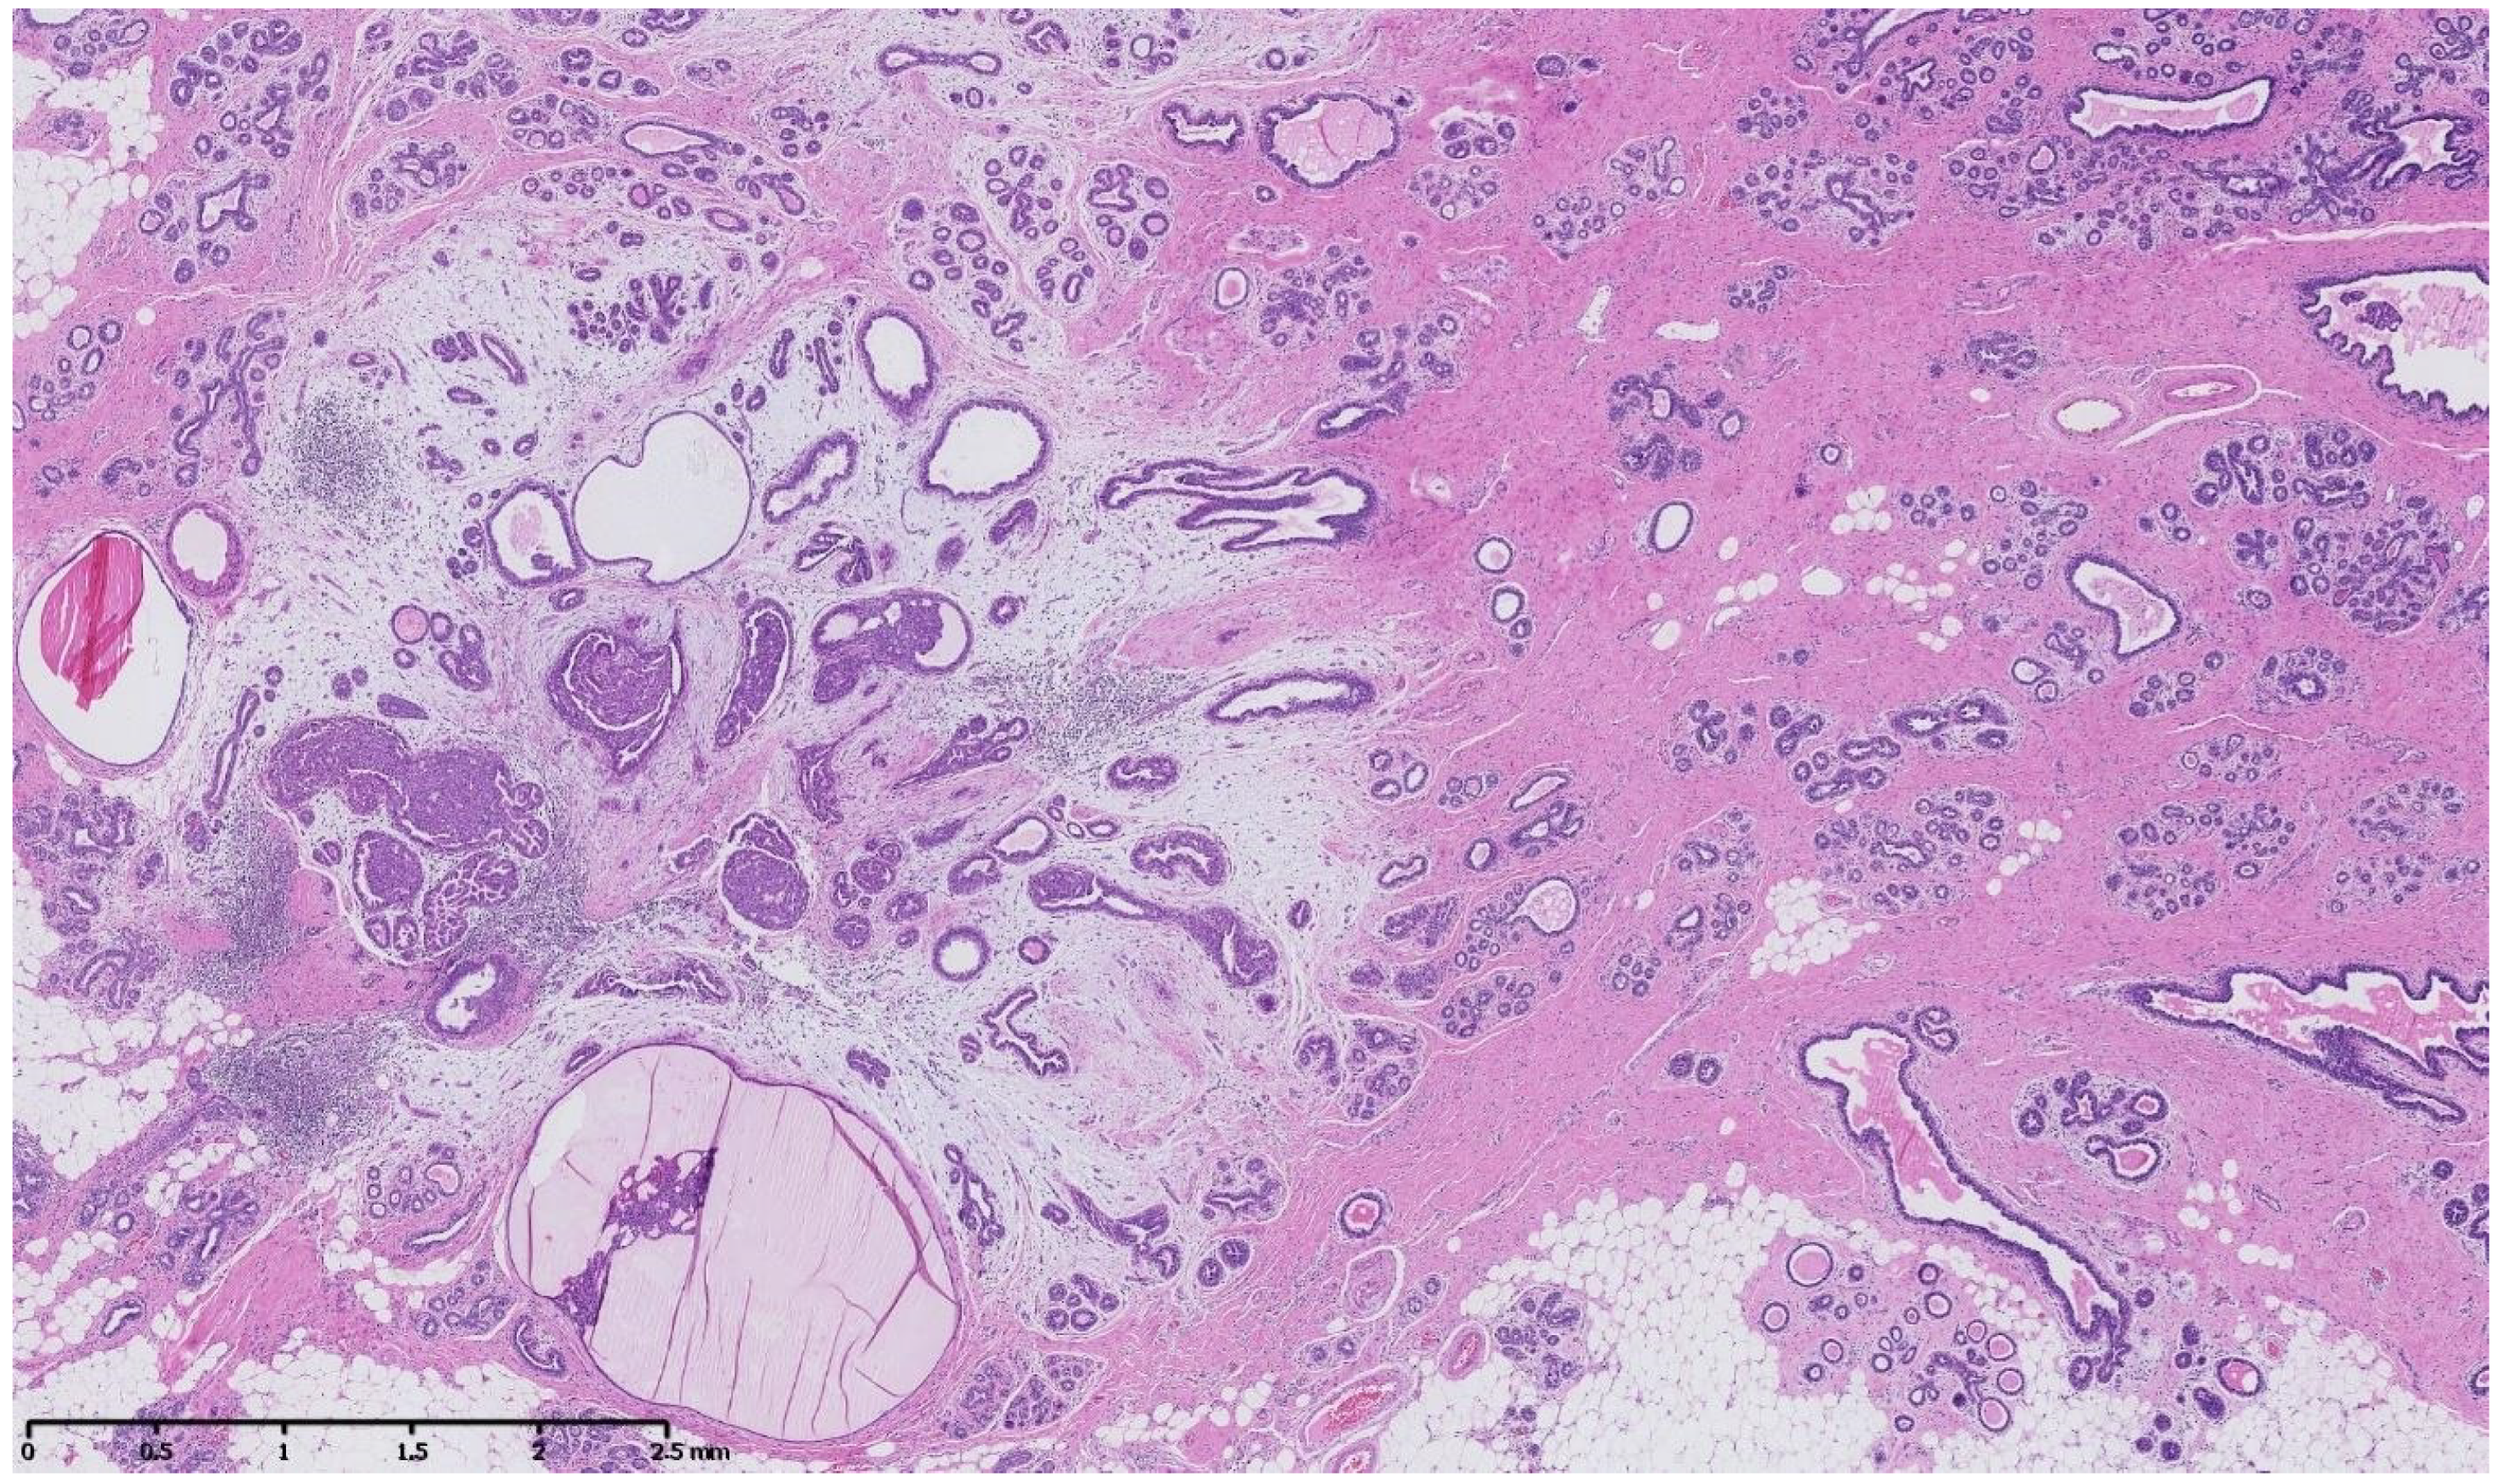

Figure 2, Figure 3, Figure 4, Figure 5, Figure 6 and Figure 7 describe a panel of different lesions observed in a patient treated for 2 years by natural estrogens and antiandrogens.

Figure 3.

Hematoxylin and eosin staining: at low magnification, the breast parenchyma shows a fibrous stroma containing an irregularly shaped lesion with a fibro-myxoïd dense stroma and inflammatory changes containing cystic ducts and hyperplastic ducts.